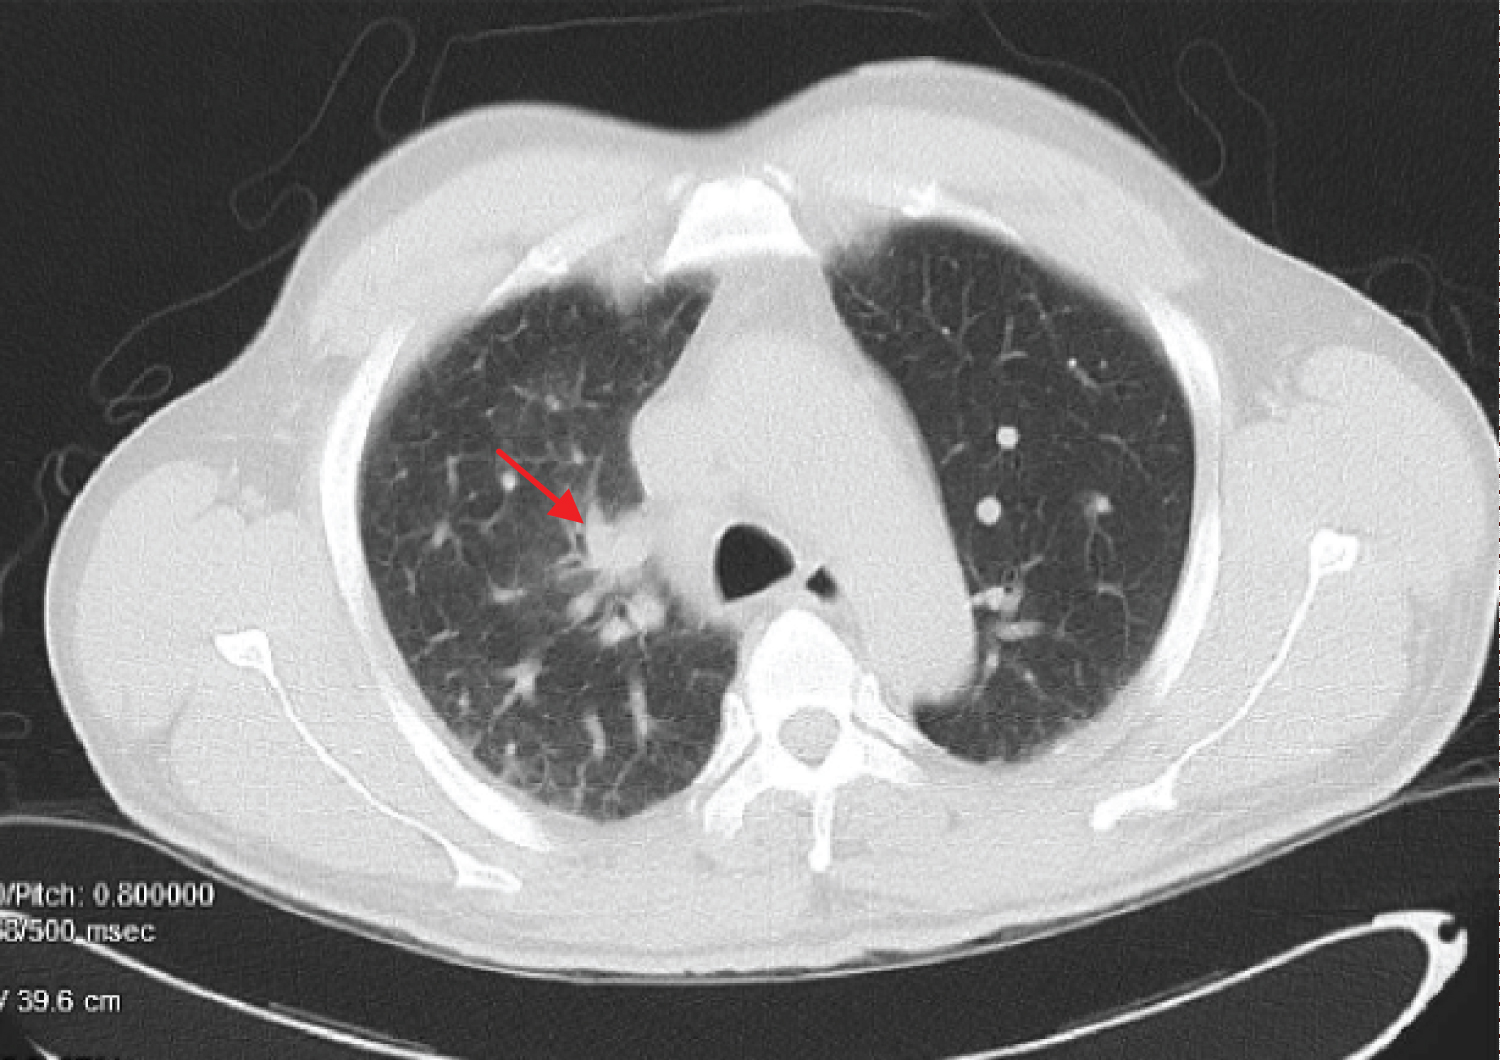

The initial laboratory values Table 1 demonstrated leukocytosis, hyponatremia, elevated BUN and Cr, deranged liver function test, Low ammonia level and slightly elevated Troponin. ECG showed normal sinus rhythm with heart rate of 112 beats per minute with nonspecific ST segment changes in lead V2 (Figure 1A). Urine toxicology screen was negative for alcohol, cocaine, amphetamine, barbiturates, opiates, PCP, and benzodiazepine. There were undetectable level of alcohol and salicylates on serum toxicology screen. Testing of the nasopharyngeal swab was positive for SARS-CoV-2 RNA. Computed tomographic (CT) of the head revealed no evidence of intracranial abnormality. CT of the chest-abdomen-pelvis (Figure 1B) revealed right suprahilar peribronchial ground-glass opacity, mild cardiomegaly, trace peripheral vascular congestion and mild hepatomegaly. There were no discernible peripheral ground-glass opacities to raise the concern for COVID19 pneumonia. Urinalysis was concerning for an infection. Blood cultures were sent for possible bacteremia.

Figure 1B: CT of the chest-abdomen-pelvis revealed right suprahilar peribronchial ground-glass opacity (red arrow), mild cardiomegaly, trace peripheral vascular congestion and mild hepatomegaly. View Figure 1B